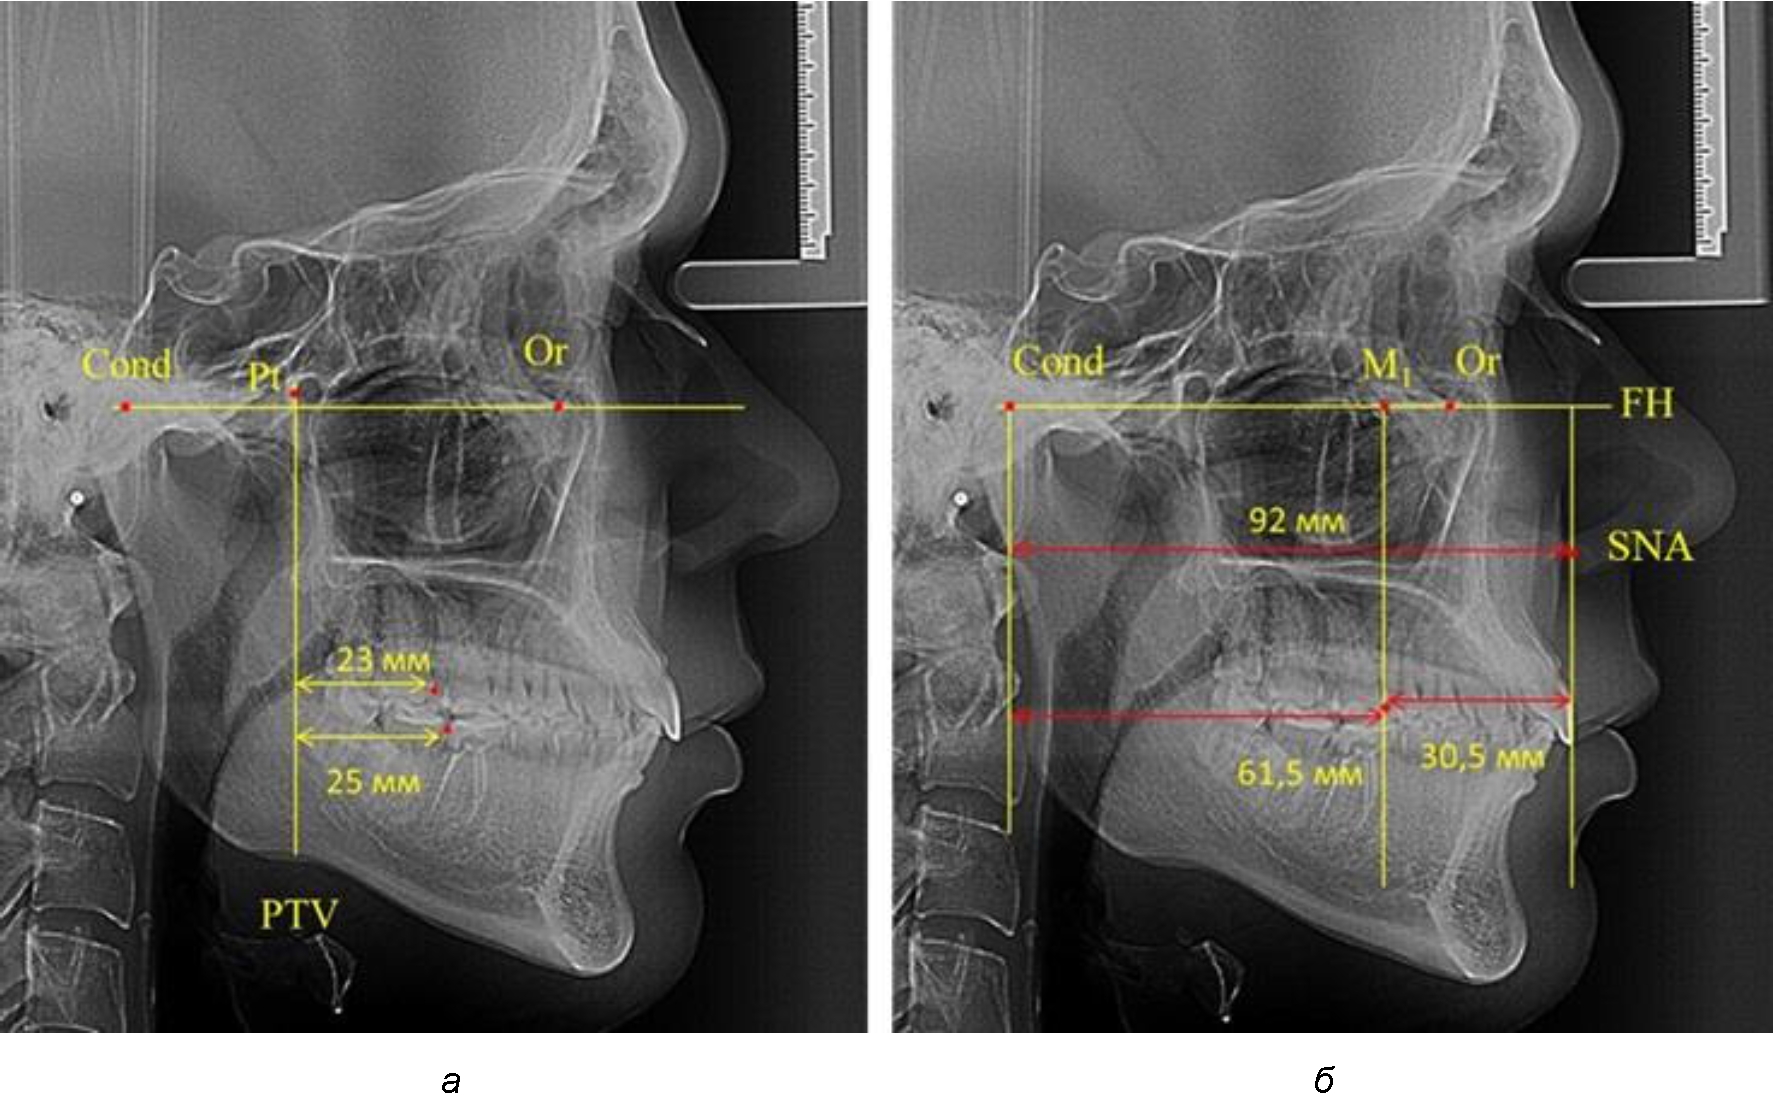

При проведении анализа к Франкфуртской горизонтали проводили передний и задний перпендикуляры. Передний спинальный перпендикуляр проходил через выступающую точку передней носовой ости (spina nasalis anterior – SNA), а задний суставной перпендикуляр опускали из кондилярной точки Cond. Молярный перпендикуляр проводили через медиальную поверхность первого постоянного моляра. Указанная вертикаль отделяла замещающие зубы постоянного прикуса от добавочных зубов (постоянных моляров), что вполне логично для анализа положения первых постоянных моляров в гнатическом комплексе (рис. 1).

Рис. 1. Метод определения положения первых верхних моляров по Ralph E. McDonald (а) и по предложенному методу (б)

Согласно указанному методу на рентгенограммах проводили Франкфуртскую горизонталь. Учитывая мнения специалистов относительно ориентиров для построения и вариабельность положения наружного слухового прохода, в качестве задней точки использовали верхнюю выпуклость суставной головки нижней челюсти («Cond»). Передняя точка традиционно располагалась на нижнем крае глазницы и определялась как орбитальная точка Or.

Находили положение точки Pt, которая располагалась на пересечении нижнего края круглого отверстия и задней стенки крыловидно-верхнечелюстной щели, и перпендикулярно к Франкфуртской горизонтали проводили крыловидную вертикальную линию, которую принято обозначать как плоскость PTV. Расстояние от крыловидной вертикальной плоскости PTV до дистальной поверхности верхнего первого постоянного моляра определяло его положение, которое, по мнению R. E. McDonald, соответствовало возрасту пациента, увеличенному на 3 мм.